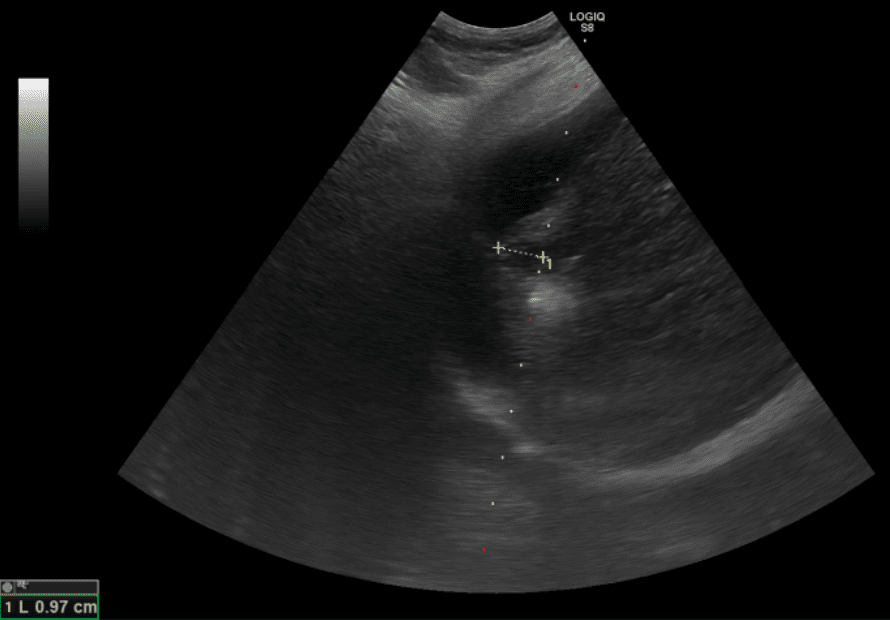

圖為超音波導引下的電燒治療,黃色標記處為肝臟腫瘤,周圍白色處為氣化範圍。

根據臨床數據,零期肝癌治療後平均存活率超過10年以上,若延誤至第二期則縮短為約5年,第三期降至2.5年,若已轉移,存活時間僅剩半年。「在第零期使用電燒治療普遍可根治,不需要化療,已經有遠處轉移才會考慮使用免疫療法及標靶治療。」鄭煜明醫師解釋,電燒治療是透過超音波導引定位,使用電極產生電流,造成離子震動產生超過60度的熱能氣化腫瘤,比起手術能更完整保留健康的肝臟組織。鄭煜明醫師進一步說明,肝癌患者平均5年的復發率高達七成,因此電燒治療對於可能復發,需要多次治療的患者而言更具優勢,且此療法住院時間短,通常三日左右即可出院。適應症方面,電燒治療適用於單顆或三顆以下、每顆腫瘤不超過三公分的個案,且腫瘤位置不能靠近心臟、肺臟等重要器官。治療前需評估凝血功能,若有凝血嚴重異常且無法透過治療矯正者,則不適用電燒治療。